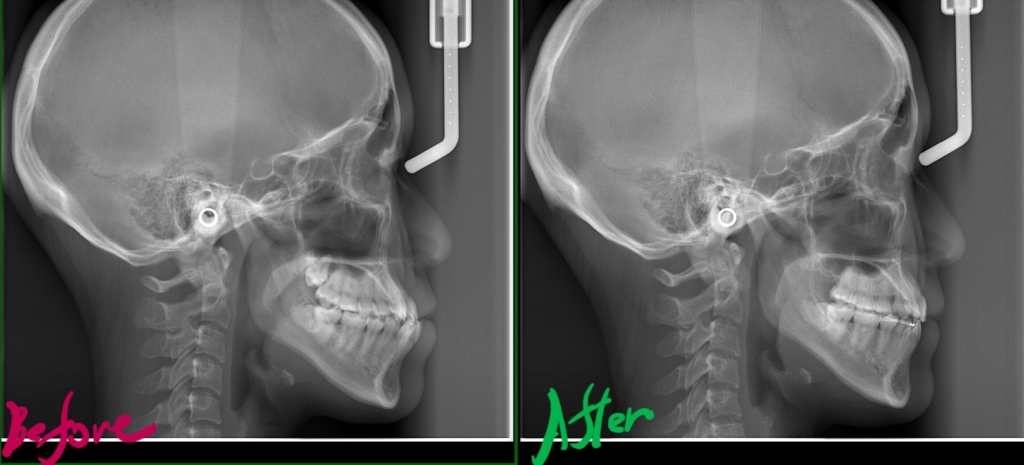

レントゲン写真で確認すると、

この患者さんの場合、

【診断】

#1.顎と歯の不調和による叢生

(前歯部の反対咬合を伴う)

#2.骨格的に下顎前突(受け口)傾向

と診断しました。

レントゲン写真でも矯正治療前後を比較してみましょう